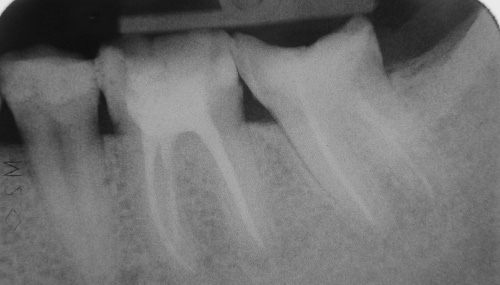

Wurzelkanalbehandlungen

Eine Wurzelkanalbehandlung wird notwendig, wenn ein Zahnnerv entzündet oder abgestorben ist.